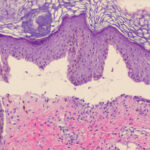

Three histologic patterns have been identified in such lesions. The first is striking basal layer vacuolization with subsequent blister formation. The second is vasculitis with subepidermal blister and pustule formation . The third and most common is a dermatitis herpetiformis-like histologic pattern. Approximately 25% of

cases are said to have a small-vessel, neutrophil-rich leukocytoclastic vasculitis beneath the blister. Histologic features more routinely identified with lupus erythematosus are not present. Another histologic finding that is not emphasized in most case reports is the presence of dermal mucin and hyaluronic acid as defined by Alcian blue stain at pH 2.5 . The frequency of mucin deposition is unknown.